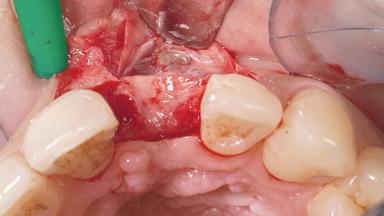

Late Placement of an Implant in a Maxillary Left Central Incisor Site

A 30-year-old female patient had lost tooth 21 and was referred to our clinic for consultation and treatment. Due to advanced apical infection, tooth 21 had been extracted two months earlier at another clinic and an acrylic-resin tooth had been bonded to the adjacent teeth. The patient desired implant treatment to avoid any damage to the adjacent natural teeth. While the patient had no history of any systemic disorder, she was a heavy smoker and exhibited medium to advanced periodontitis in the entire jaw. After the initial treatment to achieve a pocket probing depth of less than 4 mm and no bleeding on probing, a decrease in the height of the papillae mesial and distal to the extraction site and overall gingival recession were observed.

| Bone Augmentation | Horizontal|Staged |

| Augmentation Materials | Autogenous chips|Membrane |